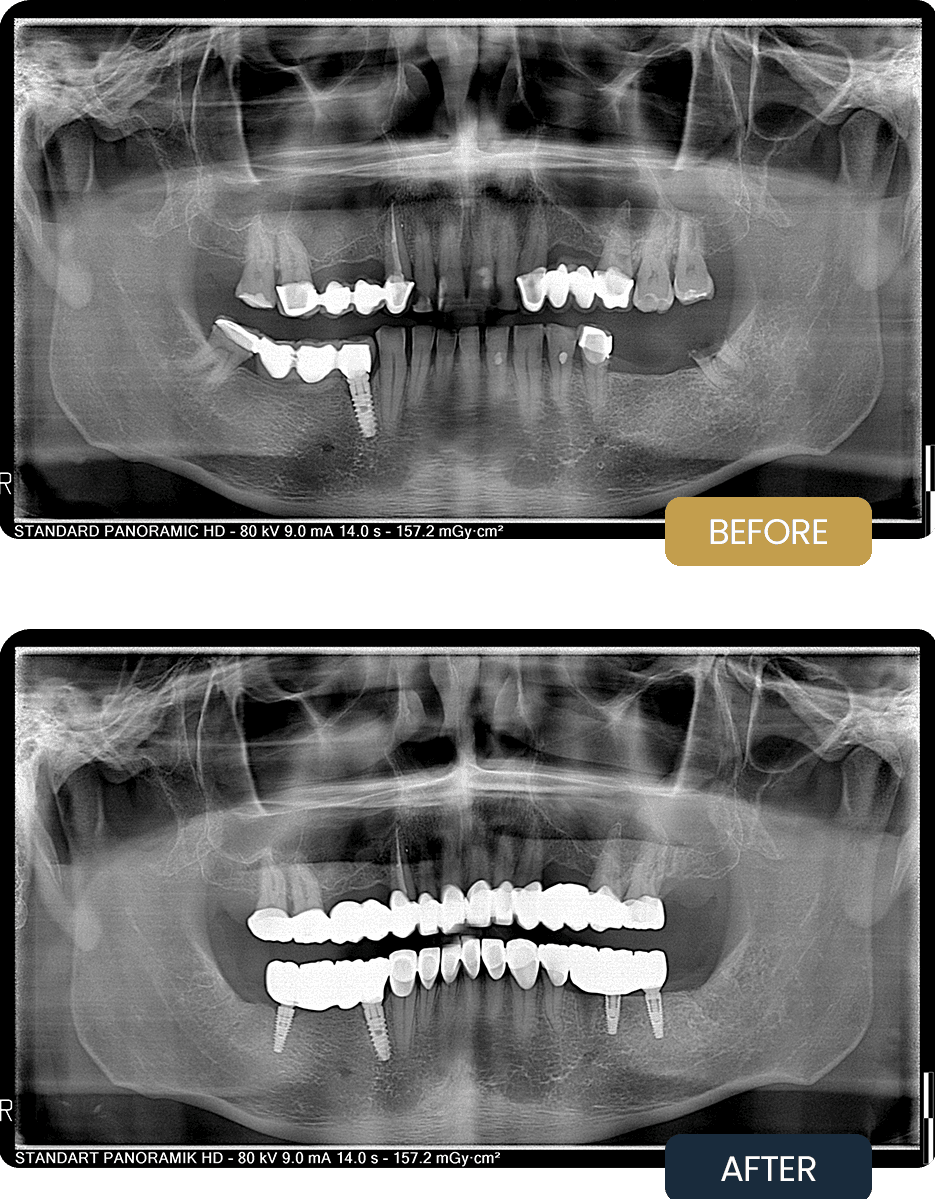

BEFORE

Rafal presented with multiple failing restorations, missing teeth, impacted wisdom teeth, and compromised dental structures across both arches.

The condition resulted in functional imbalance, reduced chewing efficiency, and aesthetic concerns.

Panoramic imaging confirmed the need for wisdom tooth extractions, implant placement in deficient areas, restorative treatment, and full coverage crown rehabilitation to restore strength, function, and long term predictability.

AFTER

Post treatment panoramic imaging confirmed stable implant placement, successful extractions, and accurately seated zirconium crowns.

The final restorations restored proper bite alignment, improved chewing comfort, and delivered a natural looking, harmonious smile with long term stability.